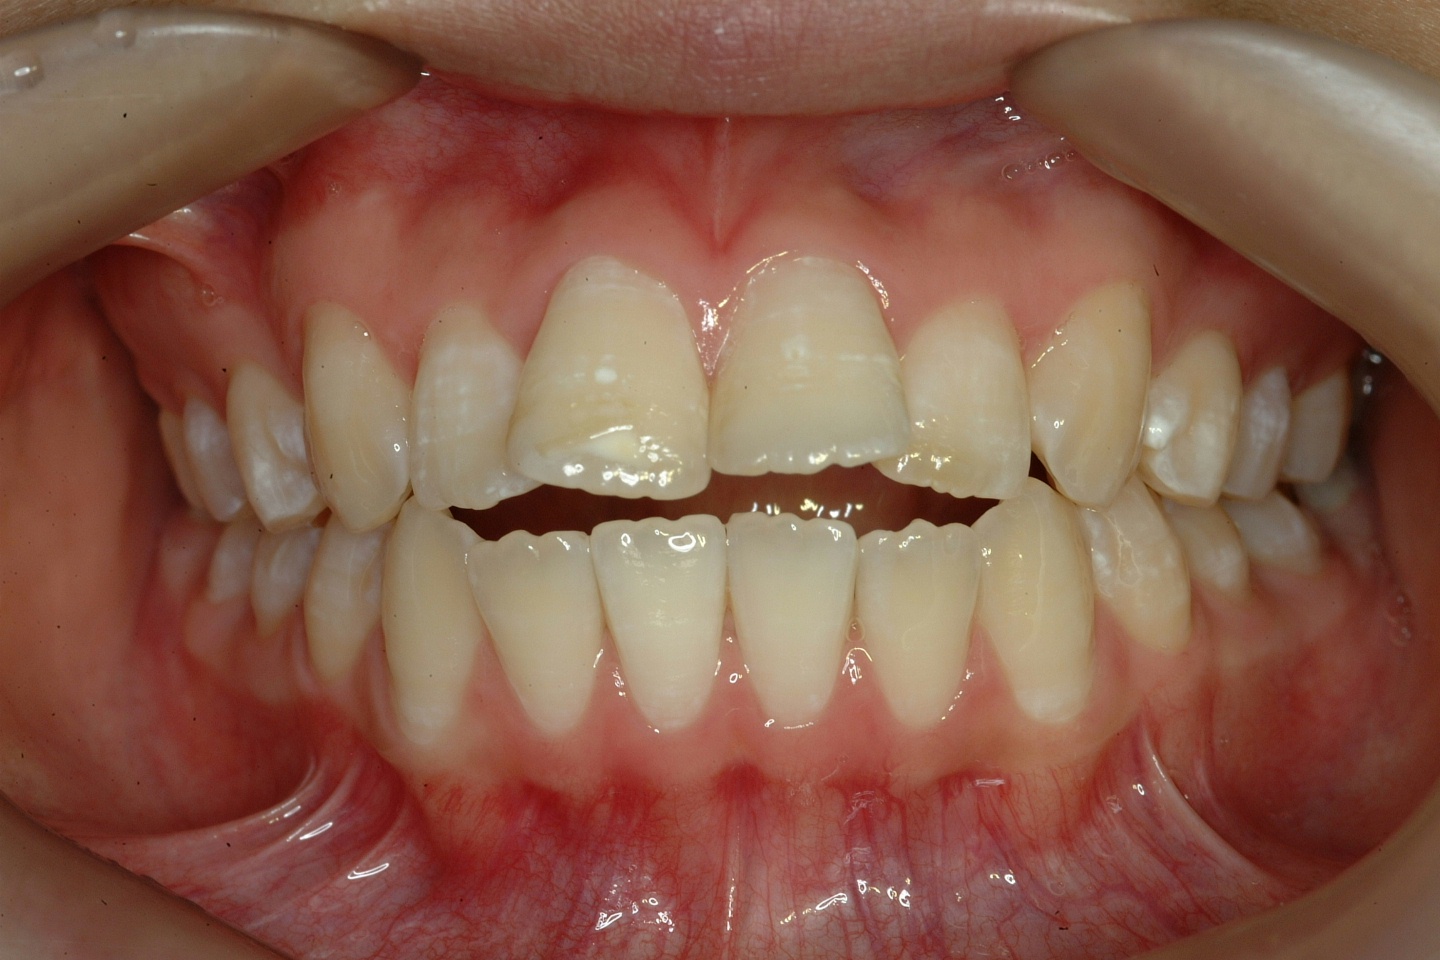

치료 전 사진입니다.